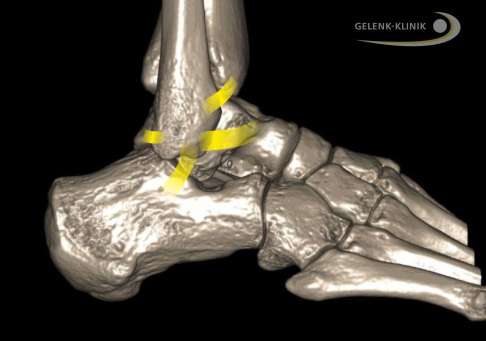

DVT-Aufnahme (digitale Volumentomografie) des Sprunggelenks: Gelb eingezeichnet sind die Außenbänder und – zwischen Schienbein und Wadenbein – das Syndesmoseband. © Dr. Thomas Schneider